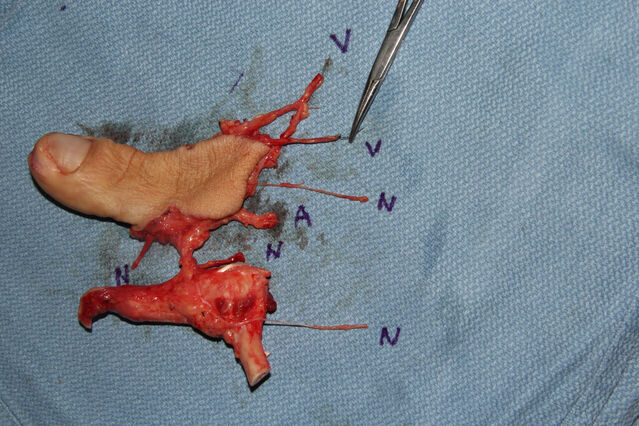

昨天的手术。

微信图片_20231008195909.jpg 微信图片_20231008195912.jpg 微信图片_20231008195906.jpg 微信图片_20231008195903.jpg 微信图片_20231008195829.jpg 微信图片_20231008195839.jpg 微信图片_20231008195836.jpg 微信图片_20231008195945.jpg 微信图片_20231008195939.jpg